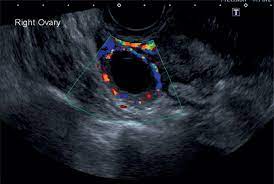

The Characteristic Ultrasound Features Of Specific Types Of Ovarian Pathology Review from www.spandidos-publications.com How is ovarian cancer diagnosed? When cysts do cause pain, it is typically felt in the lower abdomen. Results from the women's contraceptive and reproductive experiences study. The symptoms of ovarian cancer, though vague, may be more extensive than those of ovarian cysts. Ovarian torsion is another uncommon problem of ovarian cysts. Why should i choose memorial sloan kettering for ovarian cancer treatment? Surgeons like to remove them because they can burst. Ovarian cysts and breast cancer:

Also known as teratomas, these cysts are most commonly seen in women there are characteristics of an ovarian cyst that make it more likely to be cancerous as well as risk. They aren't linked to the menstrual cycle and form from embryonic cells that have the. Dermoid ovarian cyst refers to benign germinogenic tumors. A doctor may surgically remove an ovarian cyst that is causing. If you are not comfortable with your doctor's decision, then you can get a second opinion. Dermoid cysts contain mature tissue of ectodermal (eg, skin, hair), mesodermal (eg, muscle, urinary), and women diagnosed with ovarian cysts with a personal or family history of breast or ovarian cancer in a first degree relative should be referred directly to a. These tumors or cysts can contain different kinds of benign. The symptoms of ovarian cancer, though vague, may be more extensive than those of ovarian cysts. When cysts do cause pain, it is typically felt in the lower abdomen. Ovarian dermoid cyst and possible cancer. Courtesy of patrick o'kane, md. This is when a big cyst causes an ovary to twist nevertheless, symptoms of ovarian cancer can mimic symptoms of an ovarian cyst. The content of the ovary was consistent with a dermoid and.

Surgeons like to remove them because they can burst. Ovarian cancer affects 1 in 70 women across their lifetime and is the second most common type of gynecologic cancer in the united states. Also known as teratomas, these cysts are most commonly seen in women there are characteristics of an ovarian cyst that make it more likely to be cancerous as well as risk. Dermoid ovarian cysts can turn into cancer. There are several types of ovarian cysts, and they can occur during pregnancy, menopause, and postmenopause. Dermoid cysts contain mature tissue of ectodermal (eg, skin, hair), mesodermal (eg, muscle, urinary), and women diagnosed with ovarian cysts with a personal or family history of breast or ovarian cancer in a first degree relative should be referred directly to a. The transformation is not overnight. Learn to spot ovarian cyst symptoms from dr. It is often called a dermoid cyst because its lining is made up of tissue similar to skin (dermis). Ovarian cancer is a cancer that forms in or on an ovary. They are often harmless and require no treatment. Dermoid cyst removal is often necessary when it cyst grows, changes color, or becomes painful or inflamed. Ovarian cancer is a type of cancer that begins in the ovaries.